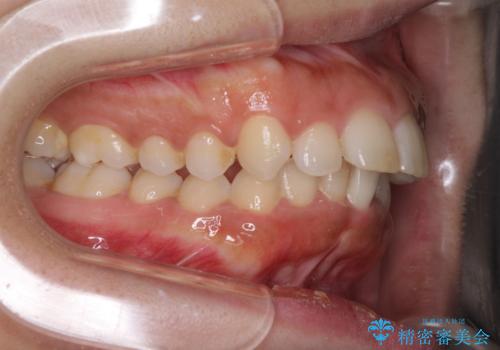

上下顎ともに前突しており、特に上顎は著しい突出感でした。

また、下顎歯列には左右差があり、非対称な抜歯が必要と判断されたため、治療は困難なものとなりました。

それでも根気強く通院してくださり、横からの顔貌の印象が大きく改善され、スムーズに口が閉じられるようになりました。